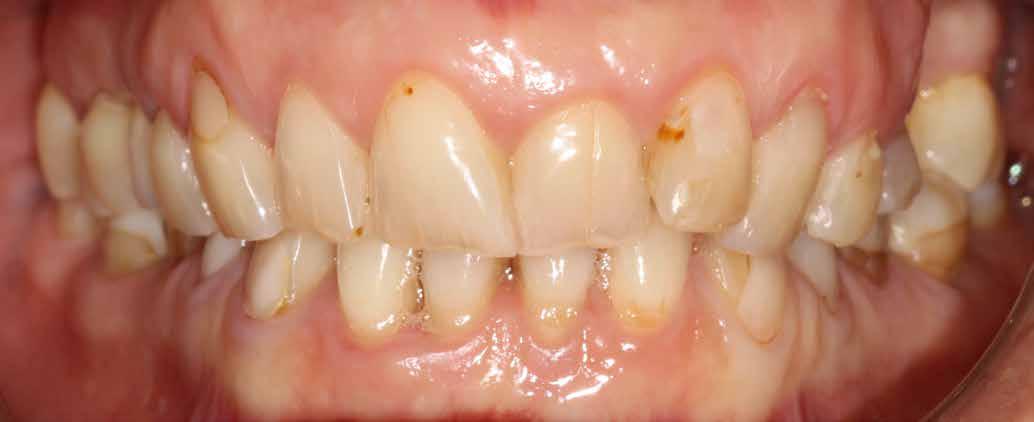

A cikkben egy fiatal nő kezelésének interdiszciplináris megközelítését foglaltuk össze, aki fogászati állapota miatt hoszszú ideje szenvedett fizikálisan és pszichésen is (1. ábra)

Amikor a 25 éves Andrea először konzultált a rendelővel, már több éve küszködött súlyos panaszokkal. Állapota két különböző betegségnek köszönhető, melyek egyrészt önmagukban, másrészt egymással kölcsönhatásban is súlyos következményekkel jártak. A fiatal nő veleszületett genetikai elváltozásban szenved, melynek tünete többek között a gyenge zománcfejlődés. Továbbá a beteget fibromyalgiával is diagnosztizálták, mely krónikus fájdalom rendellenesség, ami komoly tünetegyüttessel járó pszichés szorongás. A betegség egyik következménye az volt, hogy a páciens az elmúlt években átlagosan napi három-négyszer hányt. Az ebből fakadó savas erózió a már amúgy is veszélyben lévő fogazatot tovább roncsolta (2. ábra)

1. a–c ábrák: Kiindulási helyzet: fiatal páciens komoly fizikai és pszichés szenvedéssel.